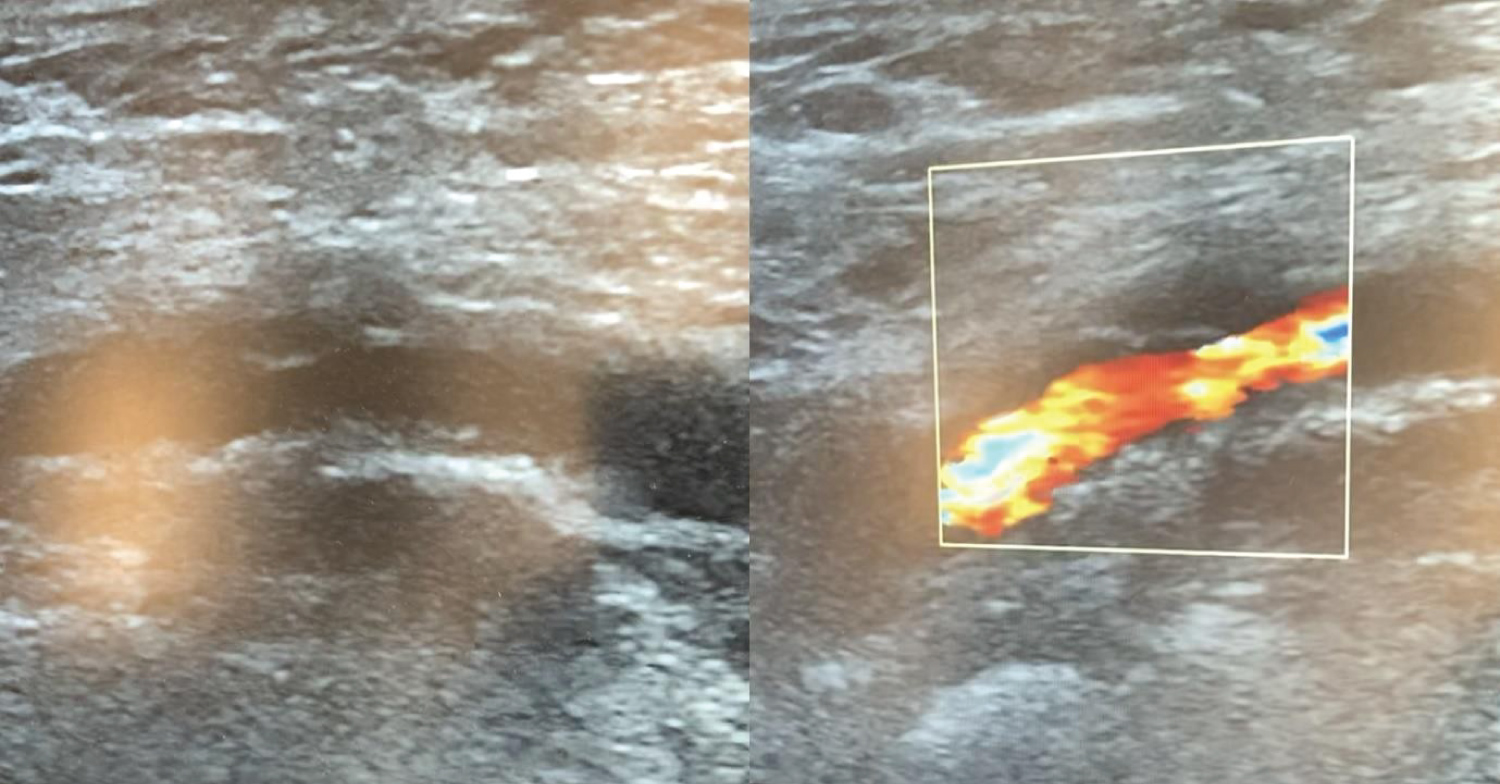

The Impella 14F sheath was advanced into the right common femoral artery under fluoroscopic guidance, and the Impella CP device was placed in the left ventricle according to the recommendations. Subsequently, a micropuncture access needle was used to pierce the hemostasis valve in the superior portion of the Impella sheath (with care to avoid piercing the Impella catheter) and a 6F sheath was advanced through a 0.035" guidewire, according to the ShiP technique [5], in order to perform coronary angiography and eventual PCI (Figure 1). A tight (> 80%) distal left main stenosis involving the ostium of left anterior descending in a left dominance system was documented. We therefore performed an Impella-assisted PCI. Using a 6F extra back-up 4 Launcher guide catheter (Medtronic, Minneapolis, MN), a provisional stenting of left main and proximal left anterior descending was performed with final kissing balloon to optimize stent apposition. The final angiographic result was good (residual stenosis < 10% and TIMI 3 antegrade flow). The procedure was carried out without complications. Hemodynamic conditions were stable during the entire procedure and vasopressors were not required. MCS was maintained for 24 hours. Hemostasis of the right femoral arterial access was achieved using a 14F MANTA VCD (Teleflex, Wayne, PA): After removing the 14F Impella sheath over a 0.035" guidewire, we used the 14F puncture location dilator (depth locator) to measure the length of the subcutaneous track from the skin to the endovascular lumen (Video 1). A 2D-color Doppler exam of the right femoral access site showed effective access site closure (Figure 2). The patient was discharged after 5 days with an almost complete recovery of left ventricle function.

Figure 2: Ultrasound examination. Effective sealing of the access site in the right common femoral artery assessed by two-dimensional and Color-Doppler examination. View Figure 2